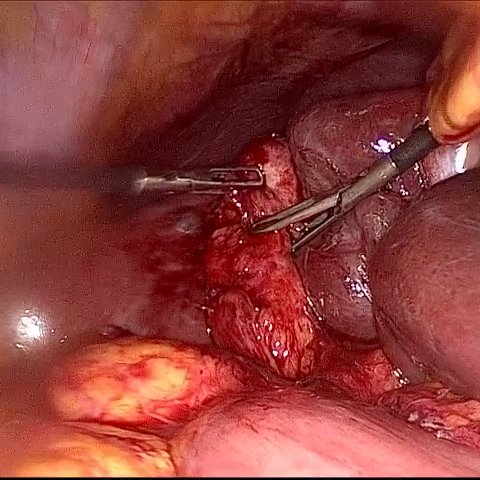

Refer to caption (a) Input Refer to caption (b) DIACMPN Refer to caption (c) Desmoke-LAP Refer to caption (d) PFAN Refer to caption (e) MITNET Refer to caption (f) Salazar Refer to caption (g) Dehamer Refer to caption (h) Ours Refer to caption (i) Target

Figure 2: Comparison of different methods on the DesmokeData dataset.

IV-C2 Qualitative Analysis

Figures 3 and 2 provide a visual comparison of the desmoking results on challenging images from the test sets. The visual results corroborate our quantitative findings. DCP not only fails to remove the dense smoke but also introduces severe color distortion. CNN-based methods like FFA-Net and MSBDN successfully remove a large portion of the smoke but tend to either leave behind a thin layer of residual haze or over-smooth the image, losing critical textural details of the tissue and surgical instruments. The Transformer-based methods, DehazeFormer and PFAN, produce significantly better results by restoring more details. However, they can sometimes struggle with non-uniform smoke distribution, resulting in regions with unnatural brightness or minor artifacts.

In stark contrast, our RGA-Net generates visually superior results that are remarkably close to the ground-truth images. It effectively removes even the densest plumes of smoke while simultaneously preserving fine-grained details, such as blood vessels, tissue textures, and reflections on surgical tools. Furthermore, the color and illumination of the restored scene appear more natural and consistent, which is a direct benefit of our model’s ability to handle both local and global features through its hybrid attention and cross-gating mechanisms. This enhanced visual clarity is crucial for improving the surgeon-robot interface in real-world clinical applications.